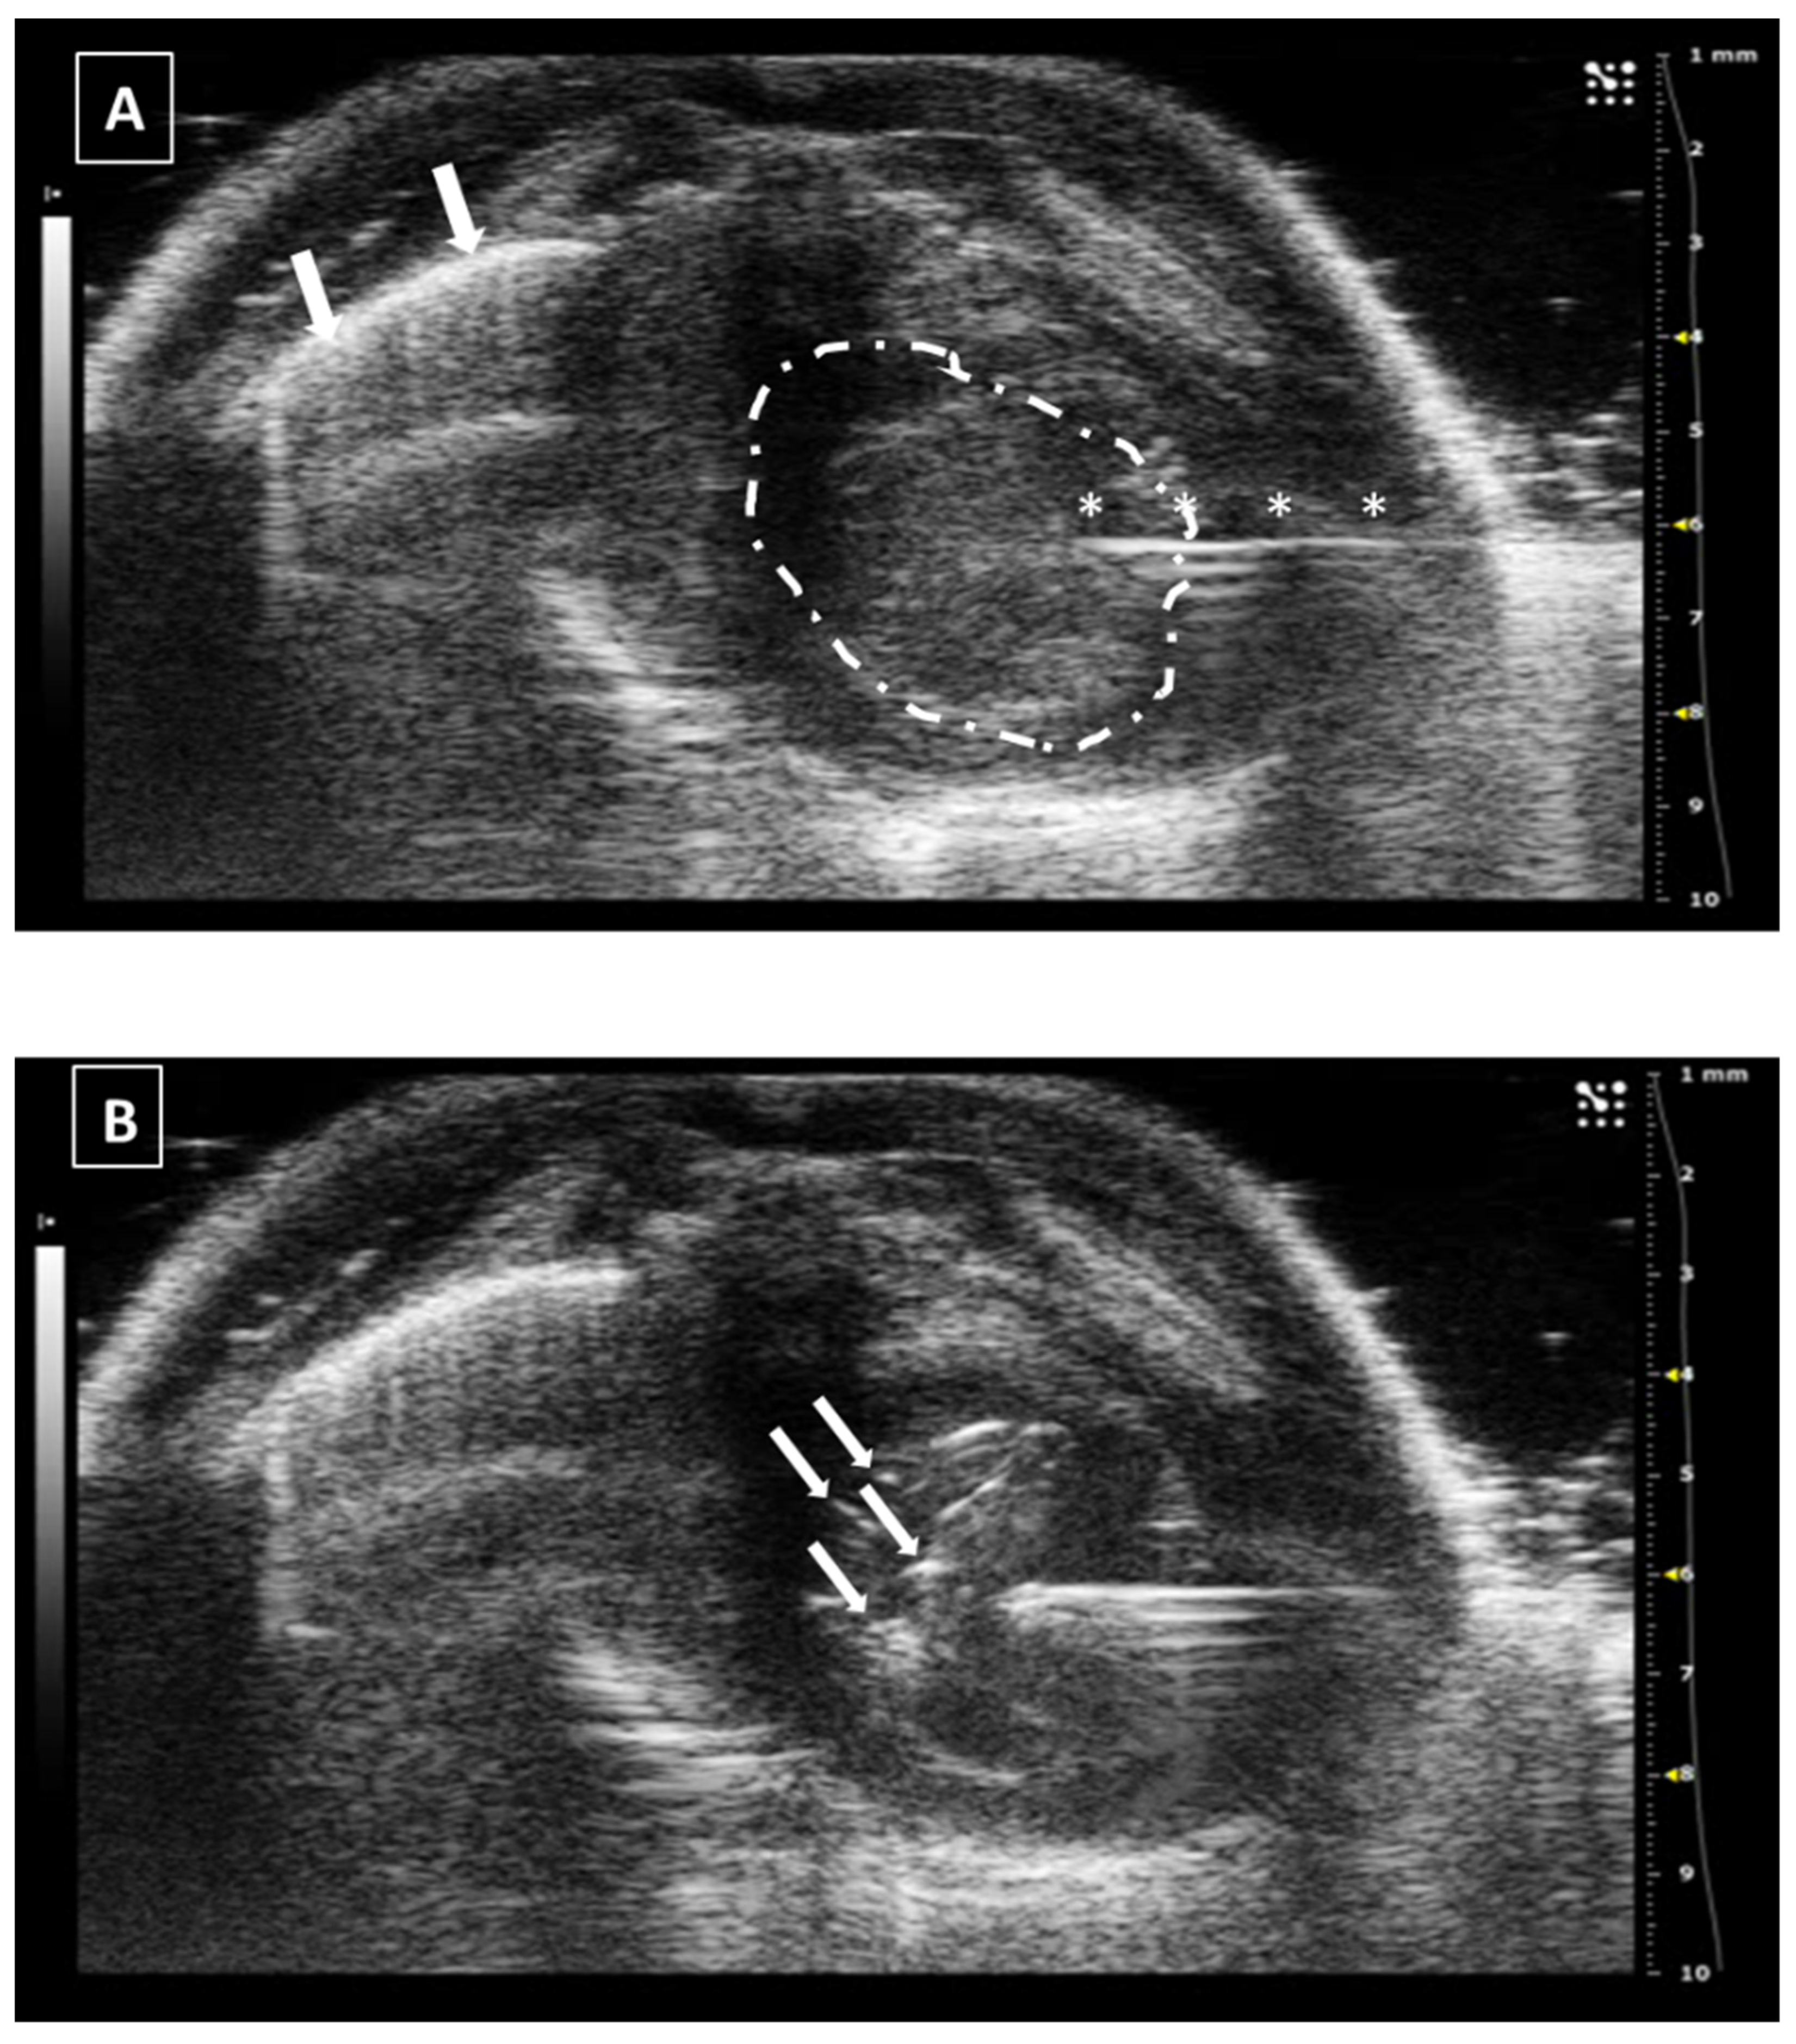

The intrahepatic injection is an easy procedure due to the size of the liver, which allows us to inject in both left and right sides of the organ. In our opinion, the right approach is easier due to the presence of the stomach on the left, which reduces the space for maneuvering. The animal is placed in ventral recumbency and hair is shaved in the cranial part of the abdomen. After localizing the desired region of the liver, the needle is moved under and parallel to the probe from the outside and into the abdomen, avoiding the rib bones. We will see a hyperechoic line going into the hypoechoic and homogeneous hepatic tissue. The injection can be confirmed with the appearance of an anechoic structure (the injected fluid) inside the liver tissue. After injecting, the needle should be kept in place for some seconds. Later, it can be removed and the organ should be examined for the presence of hemorrhages. An example of a liver injection is shown in Figure 4.

The recommended maximum volume of injection depends on the size of the organ, but in the literature, we can find volumes around 40–50 microliters [28,29,30]. An excess in the injection volume could lead to a rupture of the hepatic tissue due to a pressure increase in the tissue and this will lead to the appearance of an acute local hemorrhage, or even an hemoabdomen in case the rupture affects the Glisson’s capsule.

Figure 4. Intrahepatic injection. (A) Right side approach. Needle is marked with white asterisks. (B) Left side approach. Injected fluid is marked with white arrows. The fluid appears as an anechoic collection inside the homogeneous hypoechoic liver tissue. Images obtained at 40 MHz frequency.